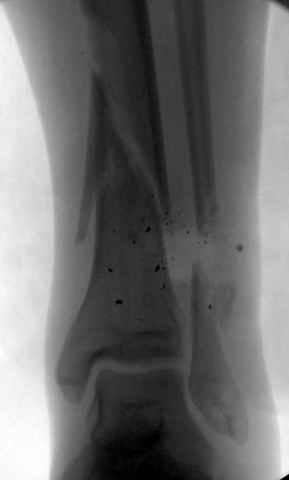

На снимках варианты фиксации малоберцовой:

№ 2-5 при огнестрельном переломе